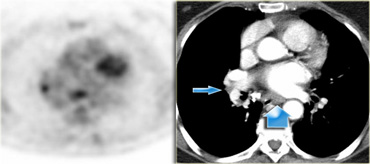

On the left a PET image demonstrating FDG uptake in a station 8 node.

On the corresponding CT image the node is not enlarged (blue arrow).

The probability that this is a lymph node metastasis is extremely high since the specificity of PET in unenlarged nodes is higher than in enlarged nodes.